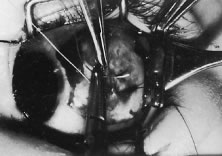

A Stevens' tenotomy hook is passed by the surgeon into the incision and is rotated so that it can be slid underneath the muscle insertion with the tip of the hook held tangential to the globe (Fig. 12). The hook should be passed 2 to 3 mm posterior to the expected location of the muscle insertion. Care is taken not to incorporate intramuscular septum or other adventitial tissue on the hook. When the lateral rectus muscle is secured with the Stevens' or Jameson muscle hook, care should be taken not to bring the inferior oblique muscle up to the insertion (Fig. 13). When the muscle is secured with the Stevens' hook, the hook and the inferior edge of the muscle insertion are elevated and a Jameson muscle hook is passed between the tented muscle tissue and the sclera to secure the muscle at its insertion (Fig. 14). Care is taken to include the entire insertion of the tendon on the hook. The tip of the Jameson hook is gently elevated by depressing the heel of the hook. This maneuver helps to ensure that the entire tendon of the muscle remains captured on the hook. A Stevens' tenotomy hook is placed in the incision, this time anterior to the insertion beneath the conjunctiva (Fig. 15). The Stevens' hook is passed posterior over the orbital surface of the muscle (Fig. 16). Gentle pressure on the Stevens' hook is directed posterior so that the check ligaments and Tenon's tissue that overlie the muscle belly are separated from the muscle capsule with blunt dissection. The hook usually is passed posterior for about 10 mm. When recessing a lateral rectus, attachments between the underside of the lateral rectus and inferior oblique are broken (Fig. 17). Two or three passes over the muscle are made, and, with simultaneous countertraction on the Stevens' hook and the Jameson hook, the conjunctiva is elevated and pulled over the tip of the Jameson hook (Fig. 18A and B).

|

The intermuscular septum and Tenon's capsule at the ball-like tip of the Jameson hook are incised with a Westcott scissors (Fig. 19). A Manhattan forceps can be used to elevate the intramuscular and Tenon's tissue to facilitate this step. Care is taken to incorporate the entire muscle tendon on the Jameson hook before this cut is made. If it is evident that there is residual tendon that is not placed on the hook, the additional tendon, intramuscular septum, and anterior Tenon's tissue are reflected over the tip of the Jameson hook with the closed tips of the Westcott scissors or a small muscle hook.

A Stevens' hook is inserted in the opening in the intermuscular septum created by the scissors and is passed anterior to the insertion. Parks has referred to this maneuver as the “pole test.” This maneuver is done to verify that the tendon of the muscle has not been split and that the complete muscle tendon is incorporated on the hook. Leaving residual slips of muscle tendon will partially or completely negate the effect of a recession procedure (Fig. 20A and B).